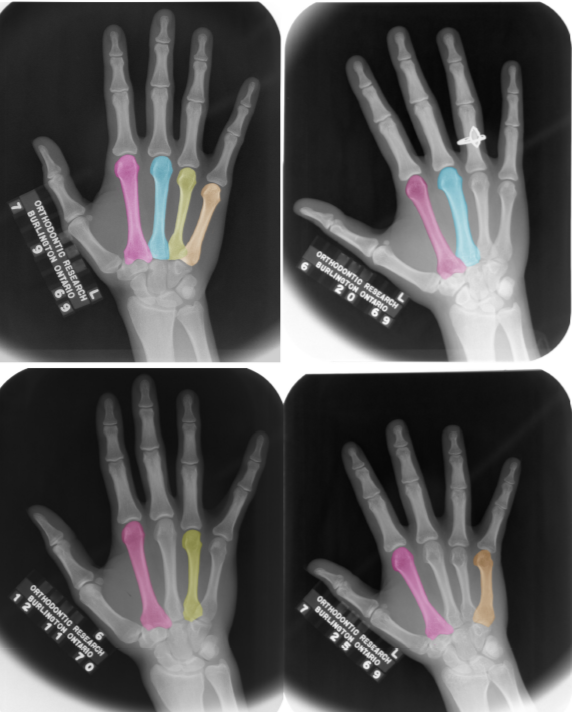

Using longitudinal hand-wrist radiographs from the Burlington Growth Study, we have demonstrated that cortical bone in the second and third metacarpals continues to thicken after epiphyseal fusion in adolesents (aged 16-20). Our findings show bone apposition occurs particularly at the periosteal surface, and slows around age 18 rather than stopping abruptly at fusion. This has important implications for how peak mone mass is defined and improves our ability to interpret adolescent growht and skeletal maturity.

Schneider, M. A., and Gilmour, R. J. (2022), Exploring radiogrammetry beyond the second metacarpal: Using the third, fourth, and fifth metacarpals to quantify cortical bone. American Journal of Human Biology, 35(3), e23831. https://doi.org/10.1002/ajhb.23831